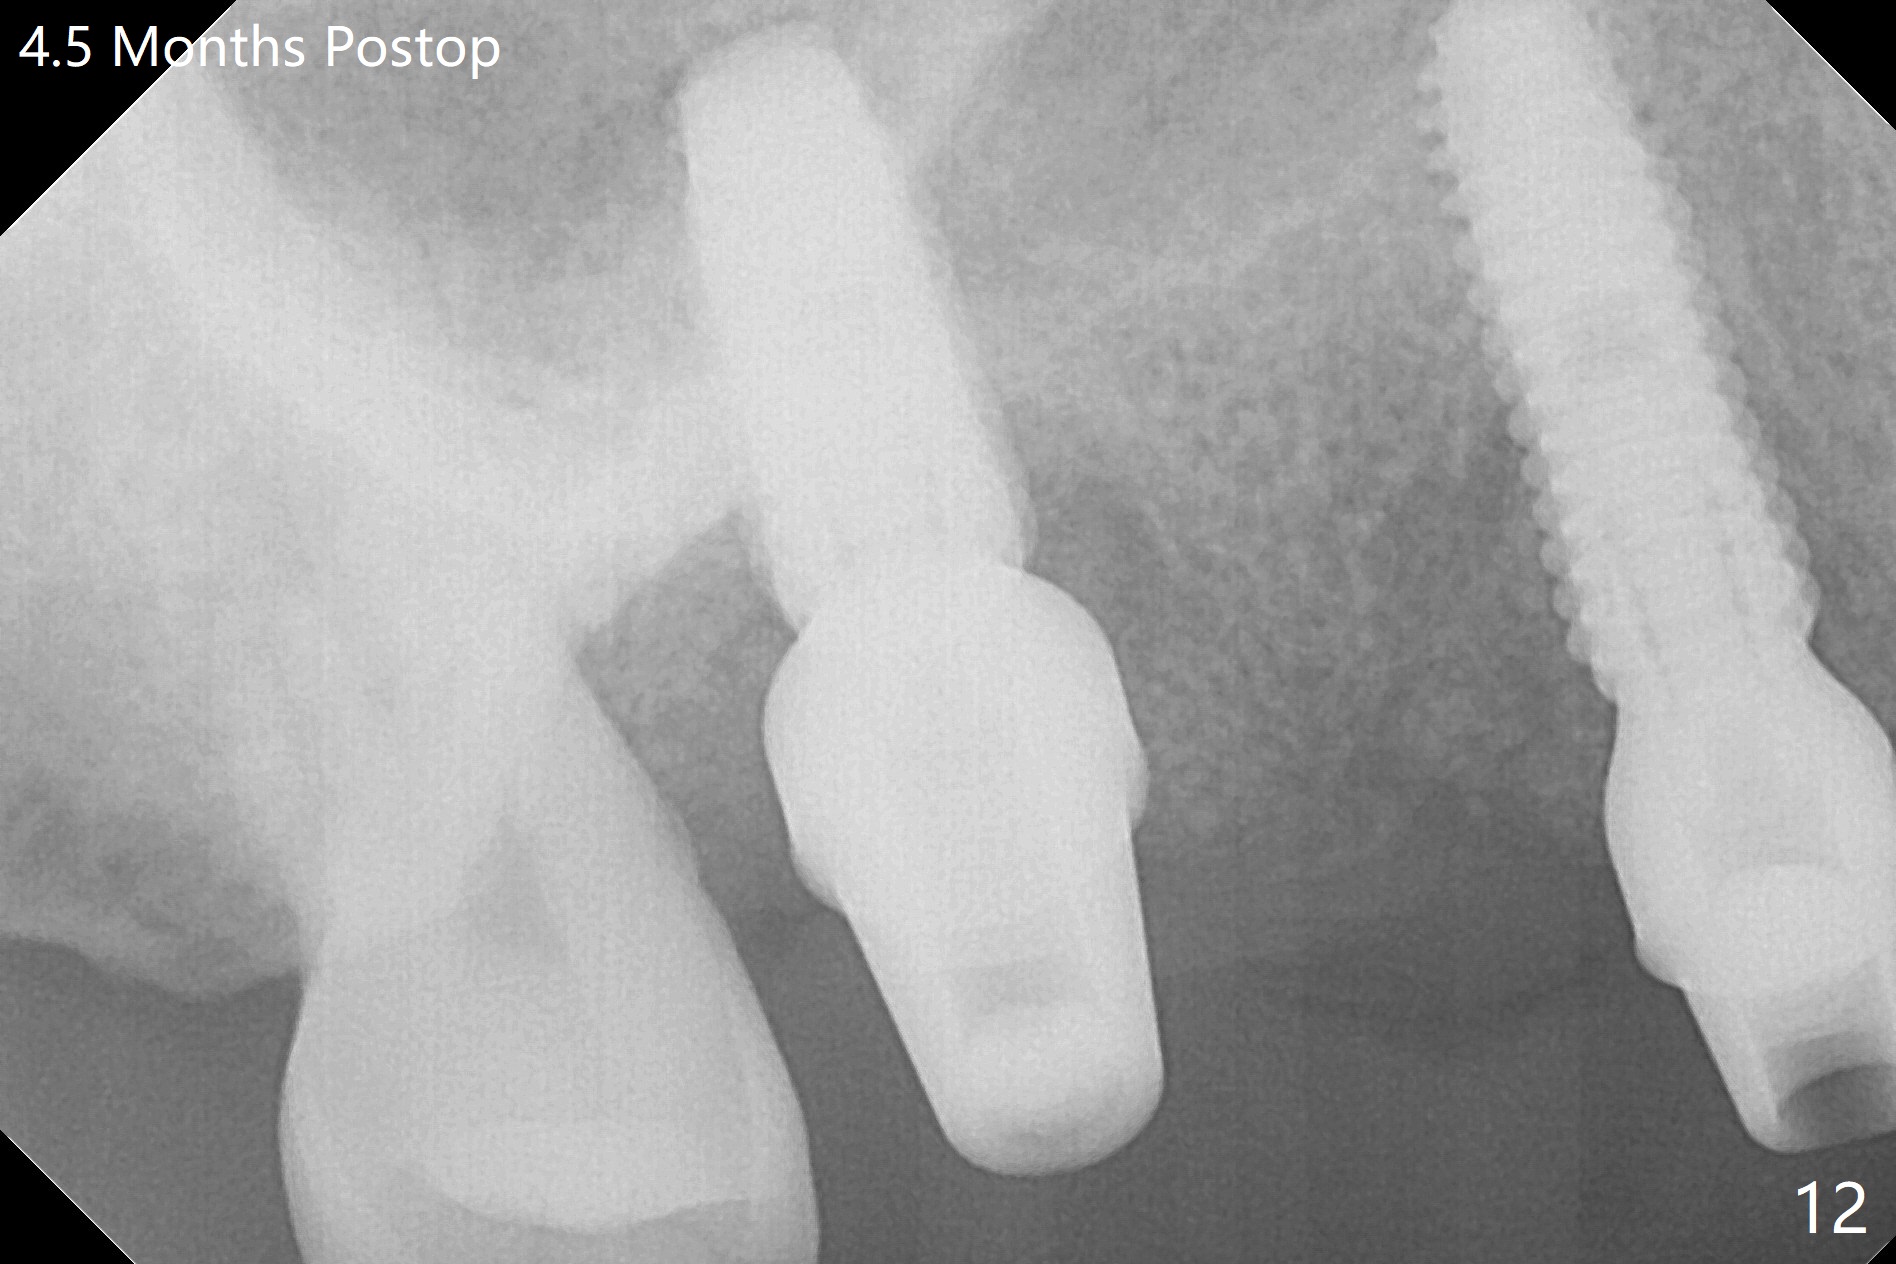

The 36-year-old man (ex-smoker, quit for 4-5 years) insists upon #3 and 5 extraction first for implants, in spite of more severe infection at #7, 14,19,30 (Fig.1-4). The gingiva around #23-26 implants is healthy 3 weeks postop (Fig.5). The initial depths at #3 and 5 are 8.5 mm (bone-level) and 18 mmm (gingiva-level (13 mm (implant length) + 5 mm cuff), respectively. When a drill penetrates the sinus floor, confirm the depth. After use of 3.8 mm drill, 4.5 mm tap drill is inserted at #3 without stability, while a 4.5x13 mm implant is placed at #5 with primary stability (Fig.6,7). Then a 5x11.5 mm is placed at #3 subcrestal proximally after sinus lift with Vanilla graft (without sinus membrane perforation; Fig.8). The implant at #5 is seated ~1 mm deeper (subcrestal mesially (^^); supracrestal distally (^)); allograft is placed around the implants prior to insertion of 6.5x7(5) and 5.5x4(5) mm abutments; last more allograft is added (Fig.9 *, 10). The implants seem to have been osteointegrated 4.5 months postop (Fig.11,12). The gingiva is healthy around the implants without bone loss 3 months post cementation (Fig.13,14).